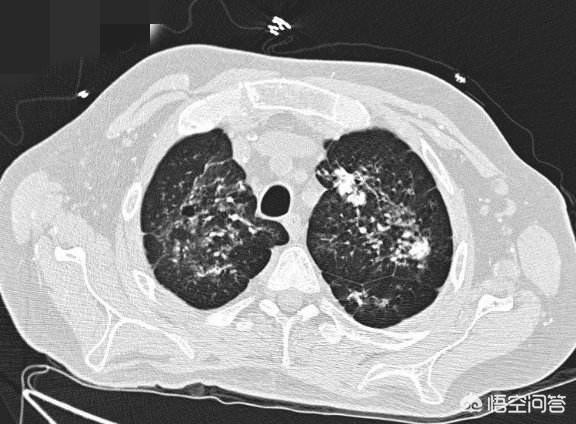

次に、肺の上葉と下葉の両方の背側節に多発する線維線条病巣の場合、以前に結核の感染があり、現在治療中で、肺にも瘢痕が残っている可能性が高い。繊維状病巣や石灰化病巣は、結核が改善したかどうかを画像診断医が評価するための重要な要素である。例えば、ある若い男性が結核に罹患し、薬を服用しているとして、2ヵ月後にCT検査を受けて吸収があるかどうかを確認し、線維化や石灰化が見られたら、それは病巣が吸収されて良くなっていることを意味するので良いことです。病巣が完全に線維化・石灰化していれば、それは古い結核であり、結核が治癒して普通に働き、生活できることを意味する。

結核が治癒した後は、結核が発生した肺の小葉や肺分節に限局した病巣が認められ、しばしば点状または結節状の石灰化病巣を伴う。二次性結核性胸膜炎の場合、胸膜に沿って大きな石灰化病巣が存在することがあることを付記しておく。

相当数の病原性結核菌が肺組織に侵入し、その中で増殖し、代謝産物を産生すると、肺組織は損傷を受け、カゼ性壊死を起こし、正常な肺組織の構造と生理機能が消失する。これらの壊死物質は酸性で、液化吸収しにくく、長期間存在することができ、身体の抵抗力が強い場合、あるいは抗結核薬の内服により、カゼ様病巣の結核菌の代謝が低下し、繁殖能力が弱まり、病巣は水分が失われて乾燥し、炭酸カルシウムやリン酸カルシウムが付着して石灰化を形成する。そして破壊された肺胞組織は弾力性と機能を失い、線維性病巣を形成する。肺の線維石灰化病巣は治癒した結核の一形態である。